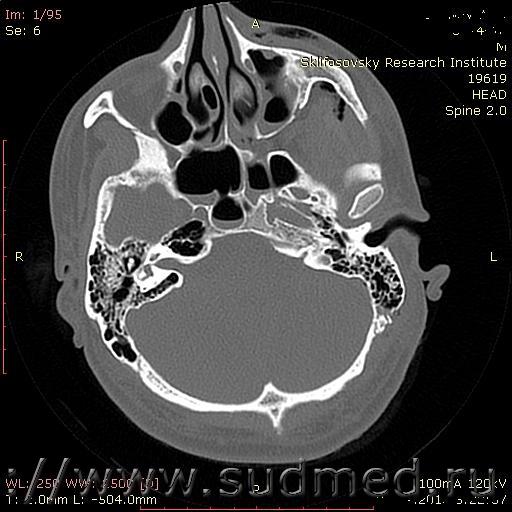

Через 8 часов после повреждения,было сделано КТ головы, на котором отмечается перелом лобной кости,скуло-орбитального комплекса слева.Эпидуральная гематома левой лобной области. Ушиб лобной доли слева с геморрогическим пропитыванием.Гемосинус.Посттравматический мастоидит.Ушиб,эмфизема мягких тканей головы и лица слева.

На рентгенограммах костей свода черепа из перечисленного, с высокой вероятностью, можно обнаружить перелом чешуи лобной кости. Перелом скуло-орбитального комплекса и перелом лобной кости в зоне крыши орбиты, с большой вероятностью, на таких снимках не будет выявлен. Без разницы - через 2 минуты, 2 часа или 2 дня от момента травмы.

Компьютерная томография (КТ), в сравнении с рентгенографией, намного более информативный метод для оценки состояния костной ткани.

По представленным Вами данным, в том числе по единственному скану КТ невозможно определенно судить о степени тяжести вреда здоровью. Это зависит от локализации перелома лобной кости. Если имеется её перелом в отделе, участвующем в формировании свода или основания черепа - будет тяжкий вред здоровью, если же лобная кость сломана в каком-то ином месте - вред здоровью средней тяжести.

Судя по описанию КТ - тяжкий вред здоровью. Без сомнения! Имеется перелом задней стенки лобной пазухи, т.е. перелом свода черепа. Есть косвенный высокодостоверный признак такого перелома - локальная пневмоцефалия (воздух в полости черепа).

Нет, такая эпидуральная гематома - не тяжкий вред. В лобной области она и вовсе может ни чем не проявлять себя клинически (разумеется, это не значит, что она безразлична для организма - просто проблемы от неё видны не столь ярко, как в некоторых других областях).